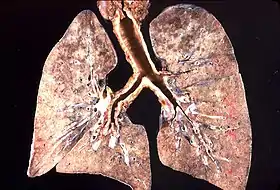

- фінальна (третя) стадія — характеризується реактивним альвеолітом з інтенсивною десквамацією альвеолярного епітелію, вакуолізацією цитоплазми альвеолярних макрофагів, плазмоцитарною інтерстиціальною інфільтрацією, великою кількістю пневмоцист як у макрофагах, так і в альвеолах.

У перебігу захворювання трофозоїти й детрит накопичуються в альвеолах до їх повної облітерації, порушується синтез сурфактанту. При цьому різко знижується дифузія газів, що призводить до дихальної недостатності.